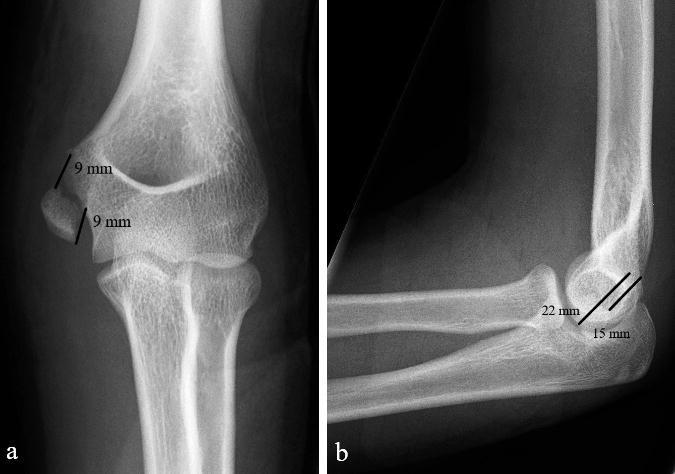

Background and purpose - Controversy exists regarding the optimal treatment for displaced medial epicondyle fractures. We compared the results of nonoperative and operative treatment and calculated the incidence of medial epicondyle fractures in the pediatric census population.Patients and methods - 112 children under 16 years old who sustained > 2 mm displaced fracture of the medial epicondyle were treated in our institution between 2014 and 2019. 80/83 patients with 81 non-incarcerated fractures were available for minimum 1-year follow-up. 41 fractures were treated with immobilization only, 40 by open reduction and internal fixation, according to the preference of the attending surgeon. Outcome was assessed at mean 2.6 years (1-6) from injury with different patient-reported outcome measures. Elbow stability, range of motion, grip strength, and distal sensation were registered in 74/80 patients. Incidence was calculated for 7- to 15-year-olds.Results - Nonoperatively treated children had less pain according to the PedsQL Pediatric Pain Questionnaire (3 vs. 15, p = 0.01) with better cosmetic outcome (VAS 95 vs. 87, p = 0.007). There was no statistically significant difference between the groups in respect of QuickDASH, PedsQL generic core scale, Mayo Elbow Performance Score, grip strength, carrying angle, elbow stability, or range of motion (p > 0.05). All 41 nonoperatively treated children returned to pre-injury sports; of the surgically treated 6/40 had to down-scale their sporting activities. The incidence of displaced (> 2 mm) fractures of the medial epicondyle in children aged 7-15 years was ≥ 3:100,000.Interpretation - Displaced fractures of the medial humeral epicondyle in children heal well with 3-4 weeks' immobilization. Open reduction and screw fixation does not improve outcome.

患者与方法-2014 年至 2019 年,我们机构收治了 112 名 16 岁以下、伴有>2mm 内侧髁突移位骨折的儿童。83 例患者中的 80 例(81 例未嵌顿骨折)获得了至少 1 年的随访。根据主管医生的偏好,41 例采用单纯固定,40 例采用切开复位内固定治疗。采用不同的患者报告结局测量方法评估平均 2.6 年(1-6 年)的结果。在 74/80 例患者中记录了肘部稳定性、活动范围、握力和远端感觉。计算了 7-15 岁儿童的发生率。